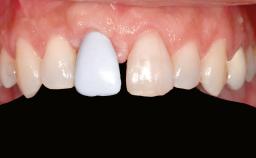

A 47-year-old woman who had suffered from aggressive periodontitis requiring a number of periodontal interventions over more than 10 years was referred by her general dental practitioner and periodontologist for bone augmentation and implant therapy. Her failing dentition had already been scheduled for extraction. The patient expressed a desire for implant-supported fixed restorations and esthetic improvement of her lower face. She had agreed to consult with a maxillofacial surgeon after the referring dentist had suggested bone augmentation. An initial examination by the maxillofacial surgeon revealed mobility of all residual teeth in a patient who was very unhappy with the function of her removable partial dentures. Due to periodontally migrated flaring teeth and loss of occlusal support, the vertical dimension of occlusion was dramatically reduced. The patient was displeased with her lower face because of deepened nasolabial, commissural, and supramental folds.